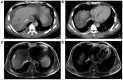

Although tumor thrombus (TT) infringement of the inferior vena cava (IVC) and right atrium (RA) is rarely observed in hepatocellular carcinoma (HCC), the prognosis for this condition is extremely poor, with a median survival time of several months, given that the condition is often diagnosed at an advanced tumor stage or combined with multiple systemic metastases. Furthermore, there is no established effective treatment for the condition. However, some investigators insist that active treatment, including surgery, chemotherapy (systemic or intra-arterial), radiation therapy, best supportive care or a combination of these, may help prolong overall survival time in these patients. The management of patients with advanced HCC and a TT extending into the RA and IVC is extremely difficult and risky. To this end, the present review assessed the literature on the clinical features and treatments of this condition in recent years, with the aim of providing assistance for clinical work.